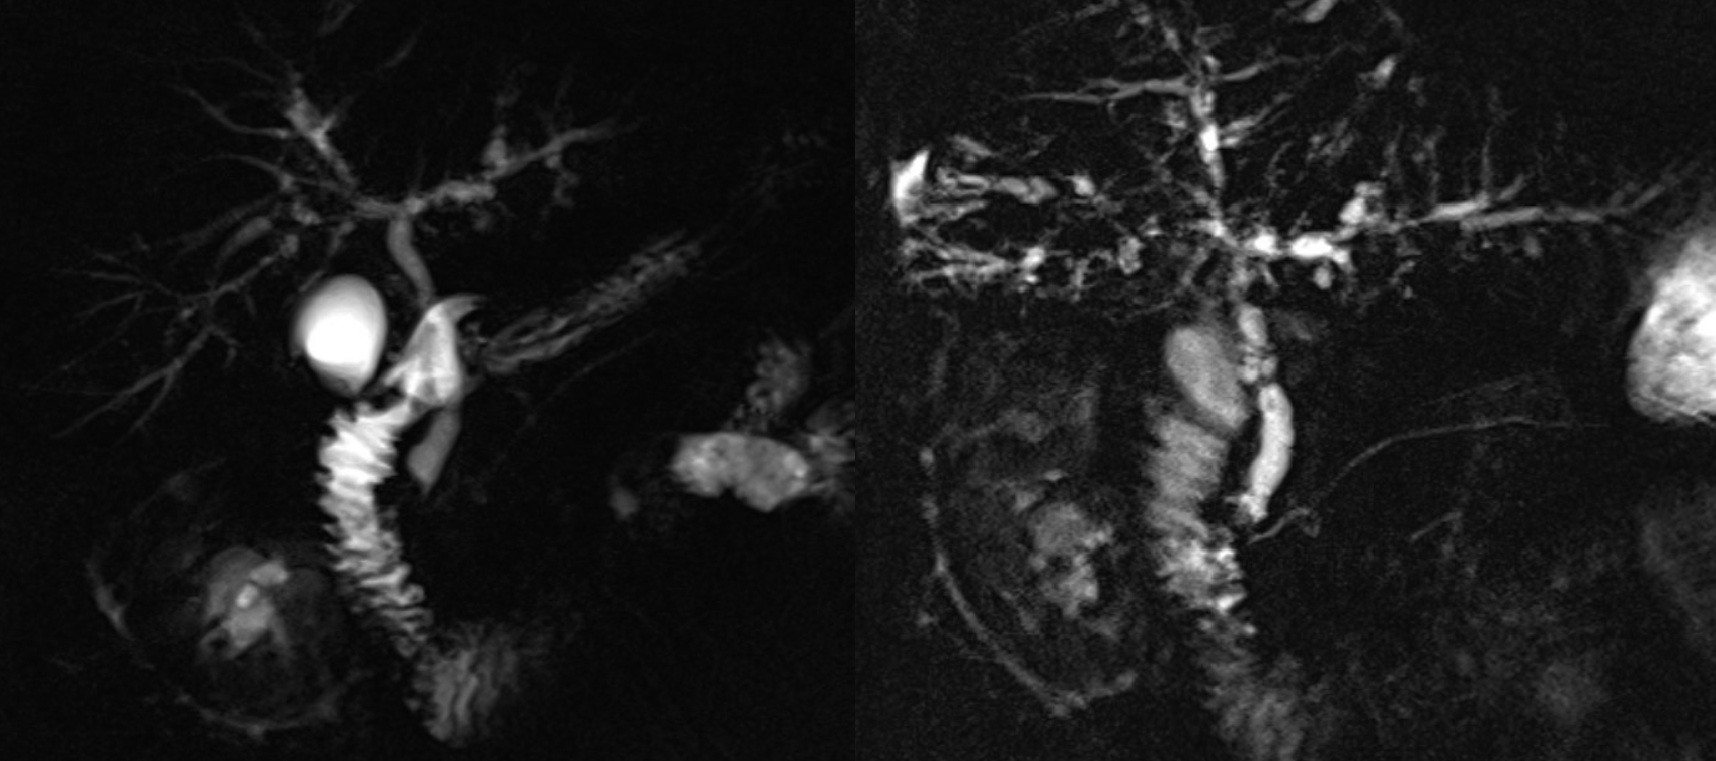

MRCP images for a second patient with PSC from one year before and after initiation of GLP-1RA therapy, with no significant interval change in the biliary architecture. The persistent ductal irregularities and stricturing are consistent with the chronic nature of PSC.